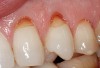

Characteristics of damage to tooth structures caused by acidity include wear on the occlusal surfaces of molars and a saucer shape on the cusps of molars (perimolysis).12 The erosion can vary from minor and subtle changes on the tooth surface, ie, loss of luster, a dull or matted look, to cupping on occlusal surfaces or incisal edges, which may extend to dentin. Usually, the erosive lesions demonstrate greater width than depth. When combined with abrasive forces or stresses, the tooth surface loss may occur at a faster rate (Figure 2, Figure 3, Figure 4 and Figure 5).

Figure  5  Loss of tooth surface and yellowing of teeth in a young patient with untreated GERD.

Figure 5